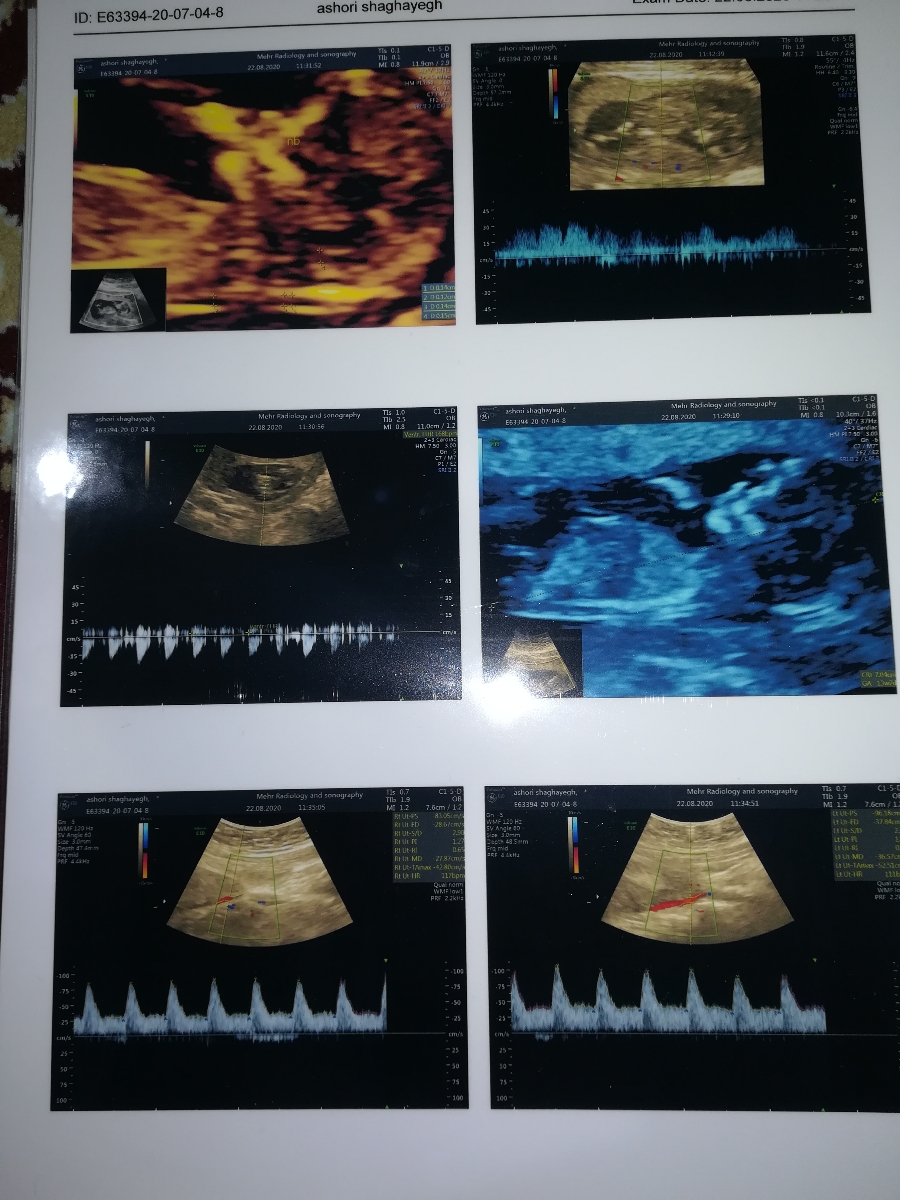

سنوگرافی nt تفسیر 🙏😘 دکتر تفسیر کنید واسم سنو

عدد ان تیت خوبه.ضربانشم ۱۶۸.حس من میگه پسره😁

طول سرویکستم خوبه

جفتت قدامی و پایینه

مراقبت کن تا بره بالا

ان تی ک خوبه ان بی هم ک دیده شده

ستون فقرات و جمجمه هم ک طبیعیه

سلام همه موارد خوبه یک دور پیچیدن بند ناف دور گردن جنین مشکلی ندارد. خود به خود با یک چرخش باز میشه. طول سرویکس خیلی خوبه ، عدد ان تی هم خوبه ، فقط جفت مارژینال است که باید استراحت نسبی را داشته باشید